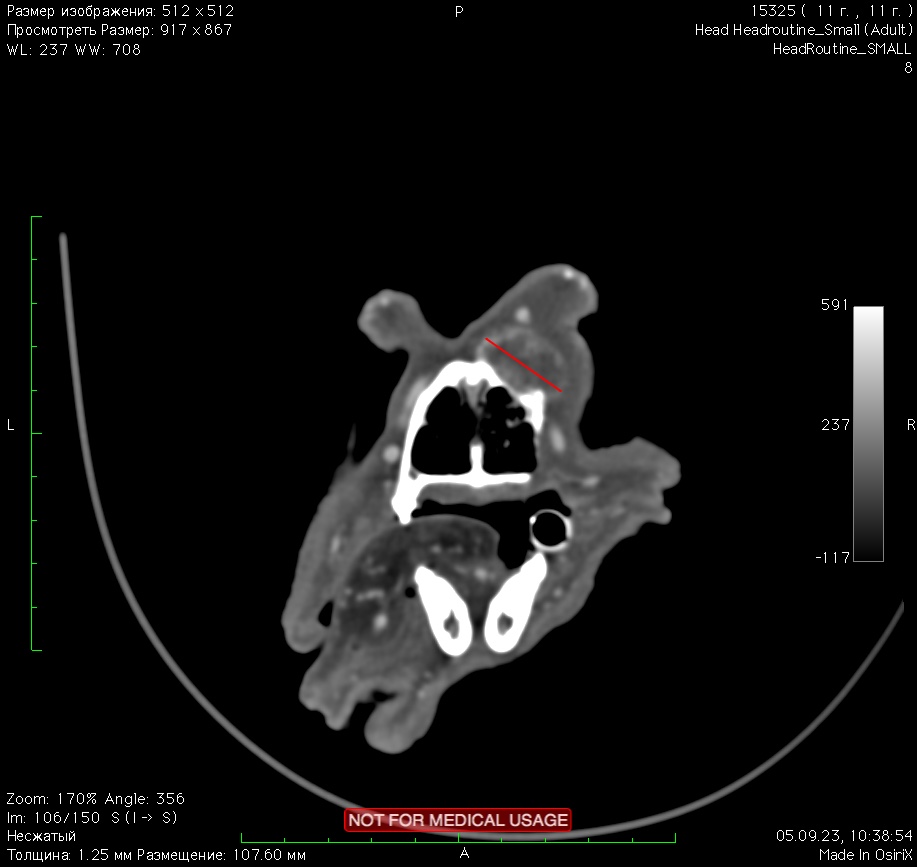

- 5.09.2023 повторное обращение в клинику по поводу растущего новообразования на спинке носа. На осмотре выявлено плотное подкожное образование, умеренно болезненное при пальпации, неподвижное, с признаками инвазии в окружающие ткани, размер новообразования 2х2 см. Проведено КТ головы с контрастом (изб. 7). Было принято решение об удалении новообразования с забором гистологического материала. Морфологический диагноз акантоматозная амелобластома с грязными краями резекции.

Изображение 7. Отмечаются структурные изменения кости спинки носа с лизисом костной ткани, визуализируется мягкотканное образование размером до 20*15*28 мм, накапливающее контраст.